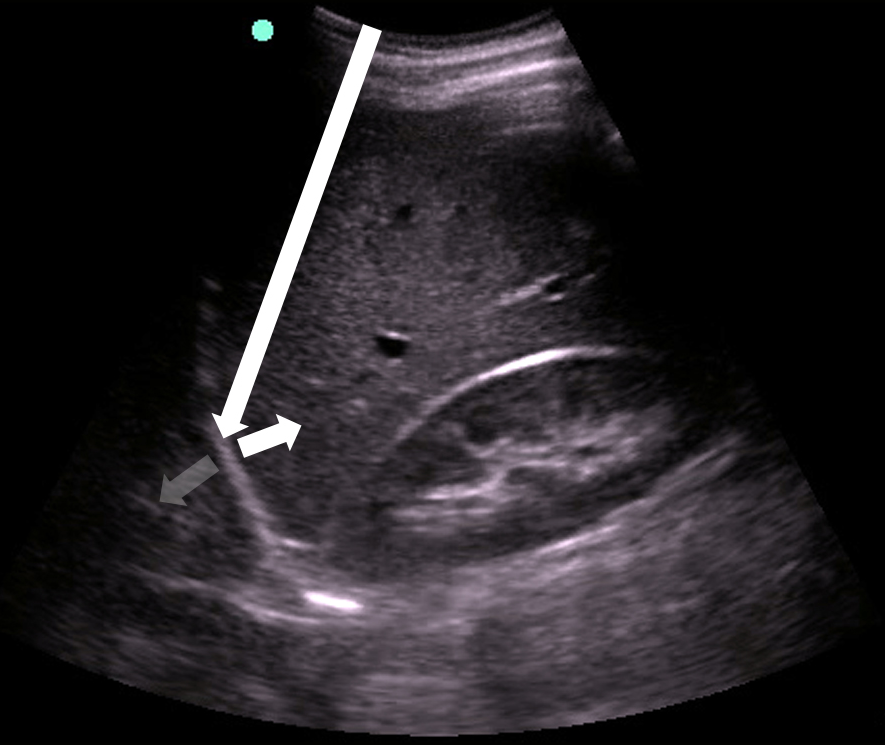

- Figure 8. Seashore sign

- Lung sliding rules out PTX16